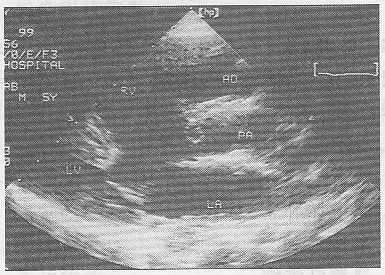

1.女,25歲,停經55天,腹痛、陰道出血1周。尿妊娠試驗陰性。結合超聲圖像(彩圖34),最可能的診斷為

正確答案:D 解題思路:宮腔內可見無回聲暗區,其內未見胚芽及胎心搏動。患者有停經,腹痛,陰道流血等流產癥狀,尿HCG陰性。